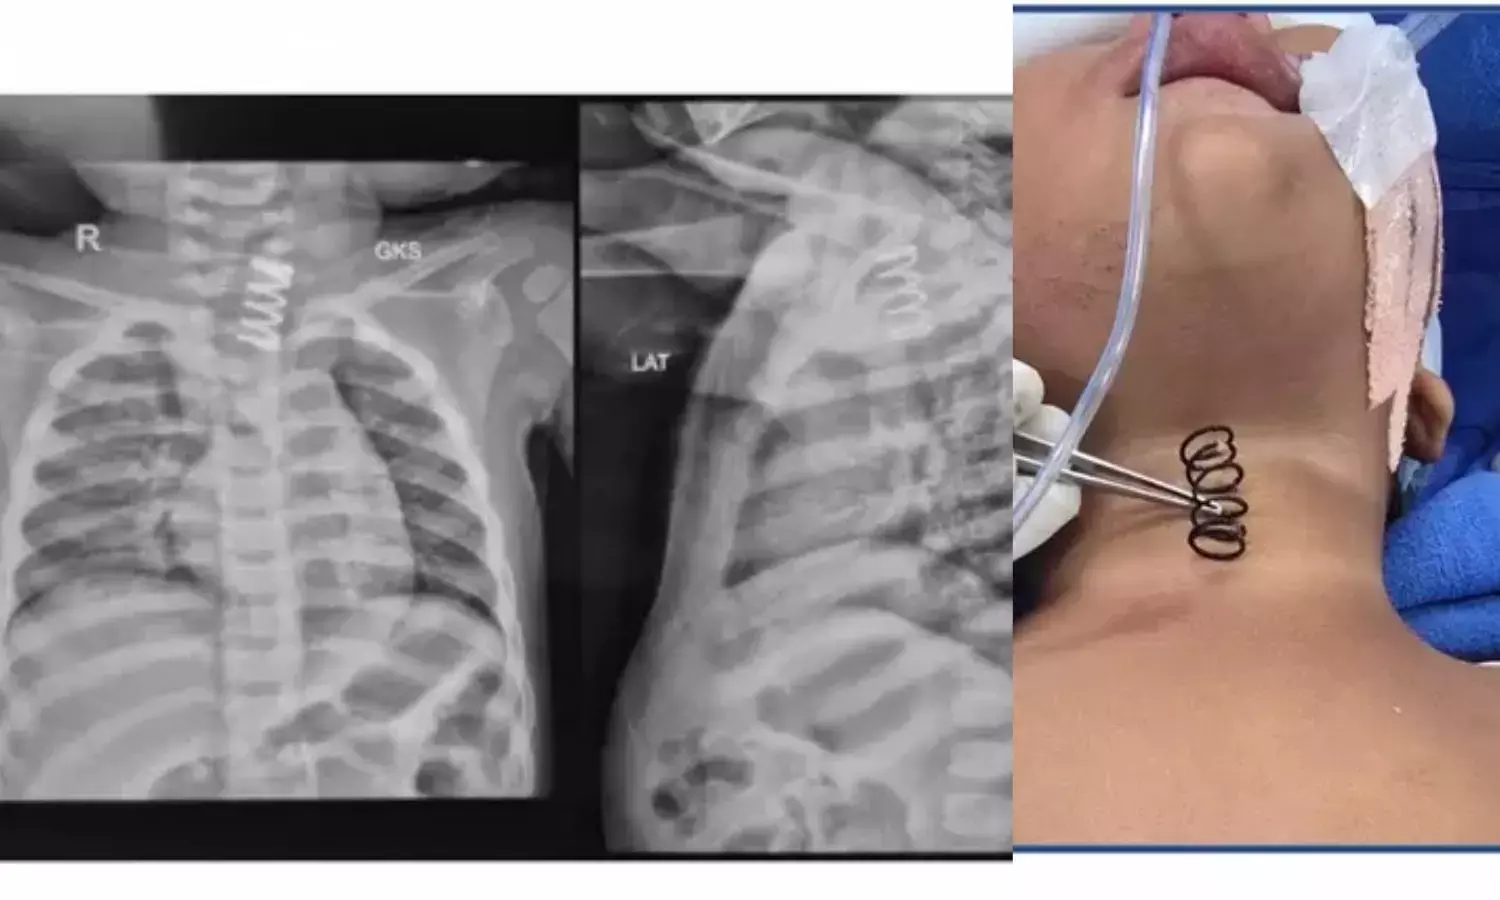

14-Month-Old Swallows Metal Spring, AIIMS Doctors Perform Life-Saving Procedure

AIIMS doctors saved a 14-month-old girl after removing a two-inch metal spring she had swallowed